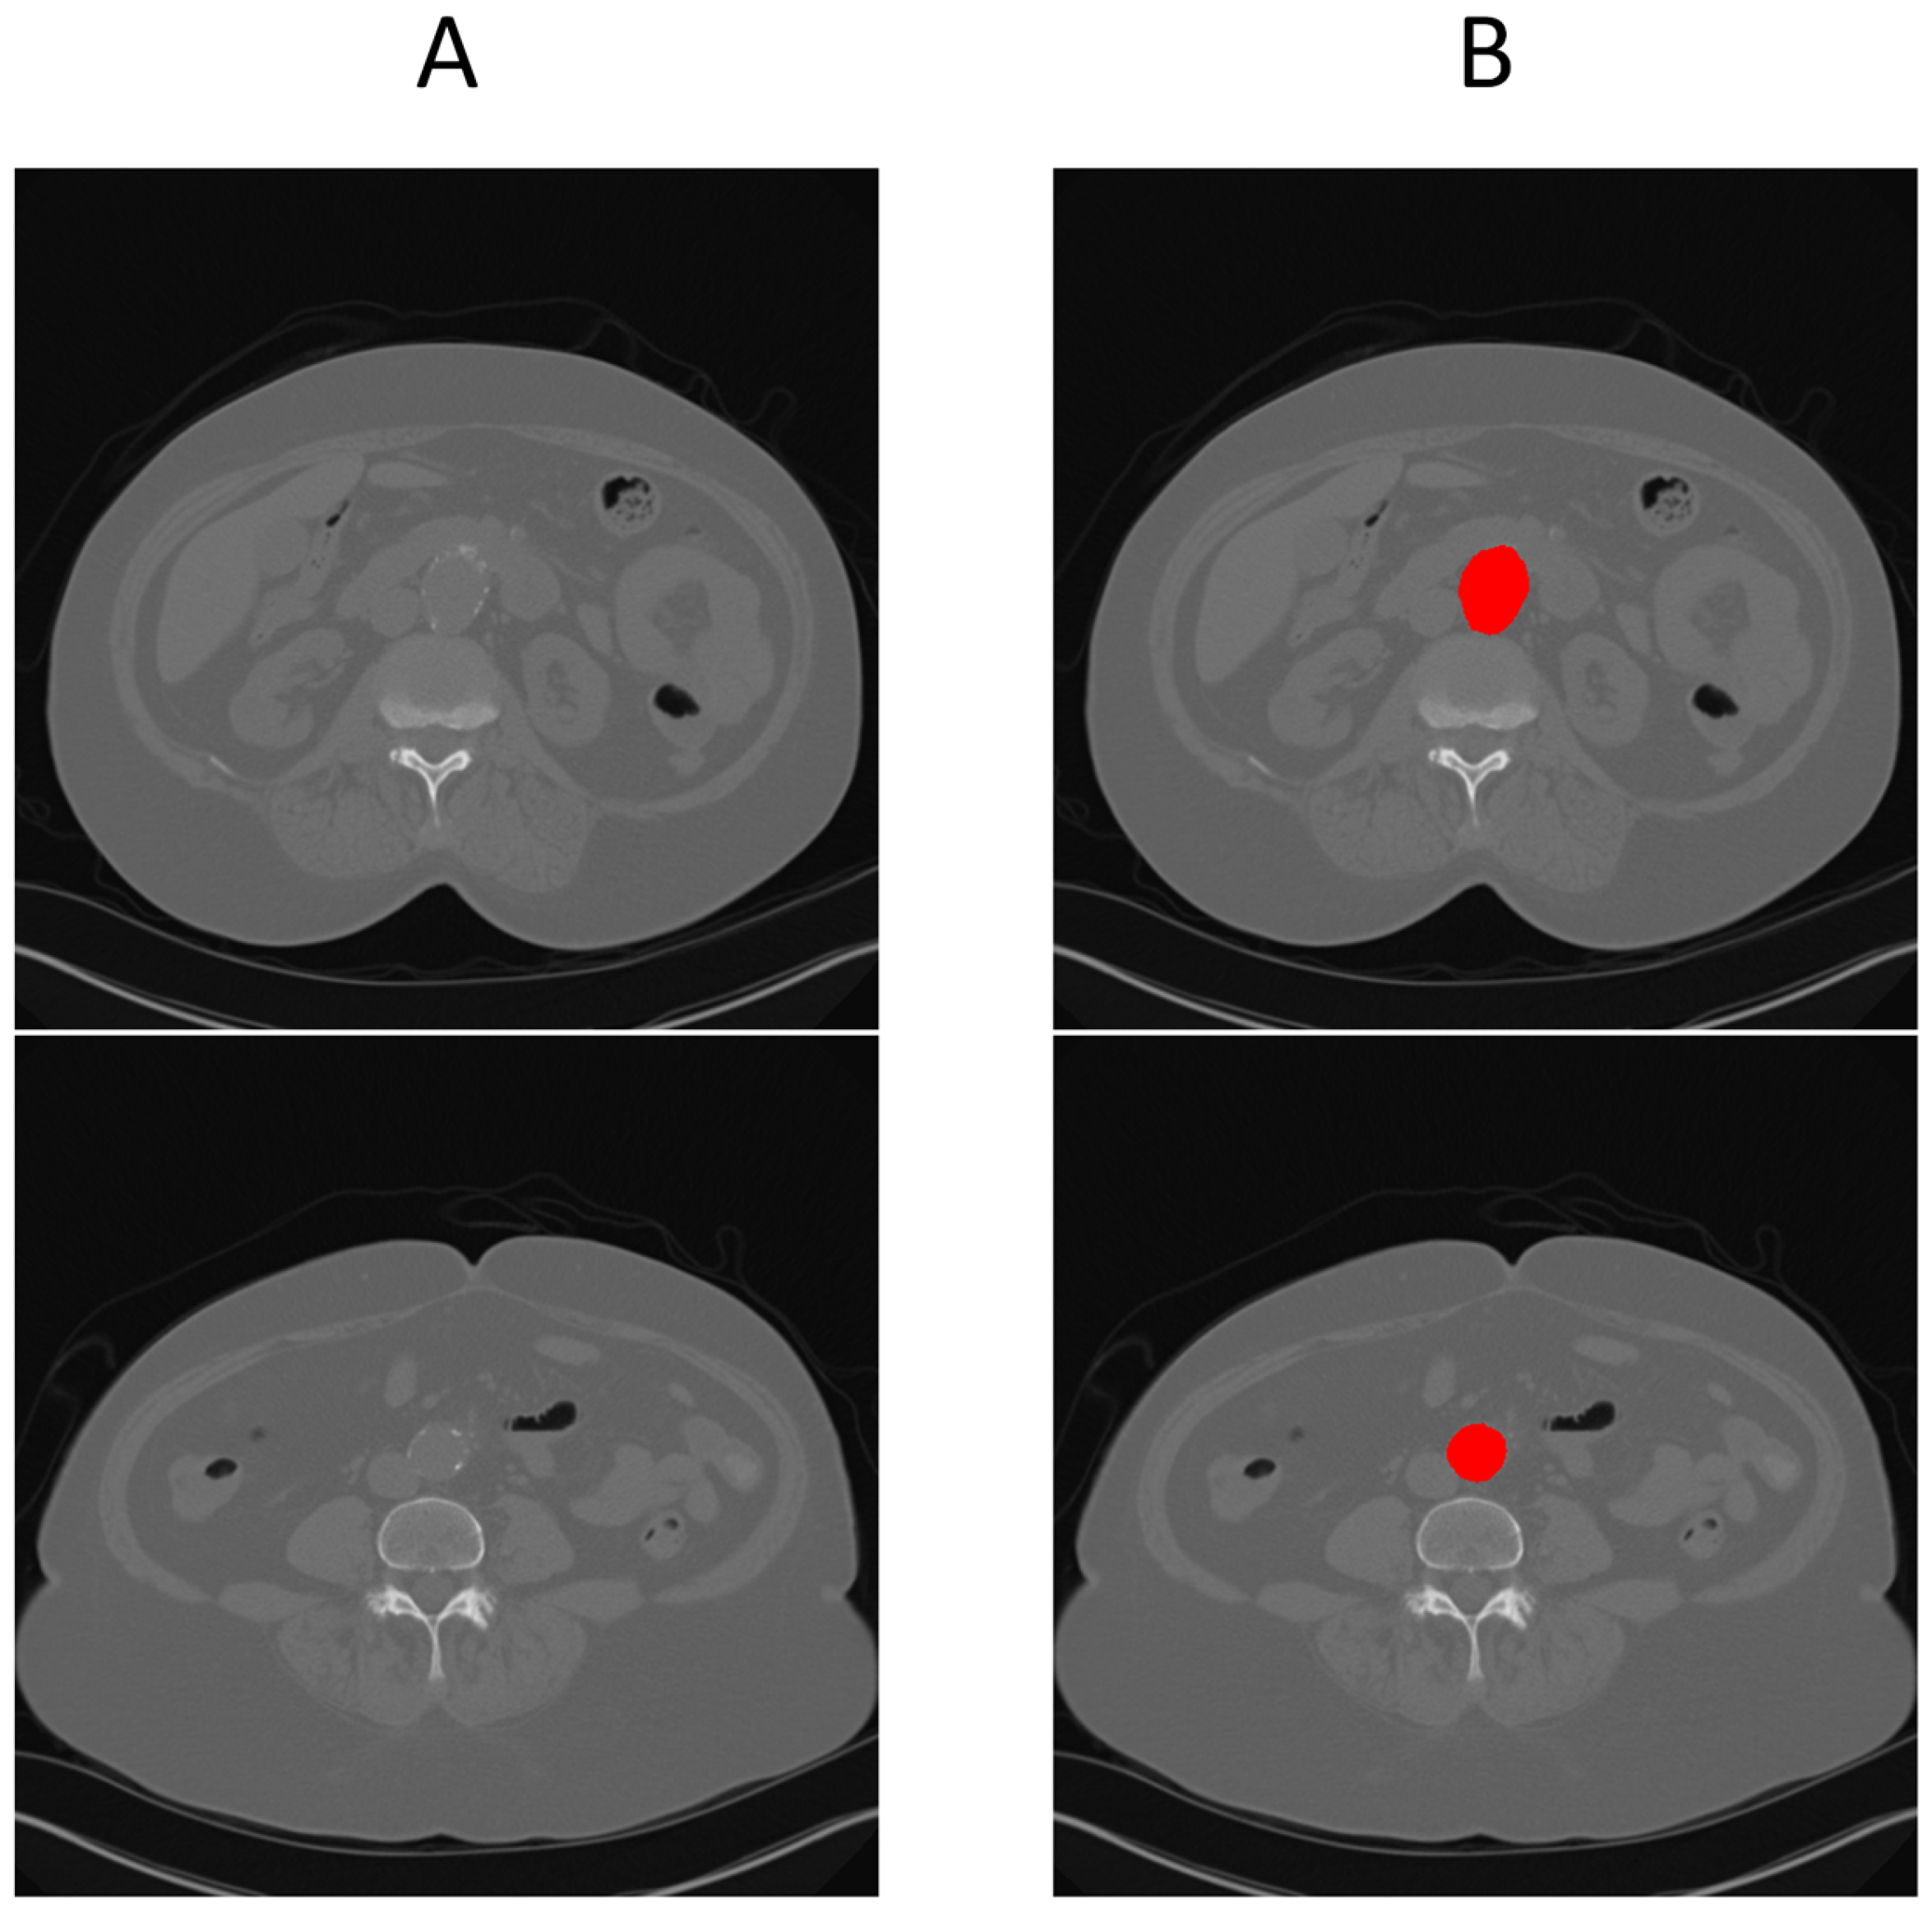

We tested this rule-based approach on 33 patient scans: 16 non-aneurysm cases sourced from our earlier study [22] and 17 cases with AAAs. The resulting confusion matrix is shown in Table 1. The expert system correctly identified 14 out of 16 non-aneurysm cases and 15 out of 17 aneurysm cases, yielding an overall accuracy of 87.9%. Precision, recall, and F1-score were all 88.2%, while specificity was 87.5%. These results demonstrate that segmentation failure in a UNet trained only on normal anatomy can serve as a reliable binary classifier for vascular abnormalities. Figure 2A shows how the UNet fails to segment the aneurysmal region, while Figure 2B illustrates successful segmentation when SAM2 is used in conjunction with UNet.

Figure 3 illustrates this full pipeline. Panel A shows the original CTA scan, while B displays the complete aorta mask generated by SAM2 after propagation over the input image. C shows the segmented mask from SAM2 output and finally, panel D highlights the aneurysm region using the manual annotation, with red indicating normal aorta segment and blue denoting the aneurysm segment. This visualization demonstrates how UNet and SAM2 operate in tandem: UNet anchors the aorta in normal regions, and SAM2 tracks it seamlessly across the aneurysm segments for full-volume segmentation. Figure 4 provides a cross-sectional view at the aneurysm’s start and end boundary, further illustrating the model’s performance.

Figure 3. Full aneurysm segmentation pipeline. (A) Original CTA scan; (B) SAM2-generated aorta mask overlaid on the scan after propagation; (C) Binary segmentation mask produced by SAM2; (D) Manual annotation showing normal aorta (red) and AAA region (blue). The sequence shows how the proposed approach extracts an aneurysm despite having no aneurysm labels during training.